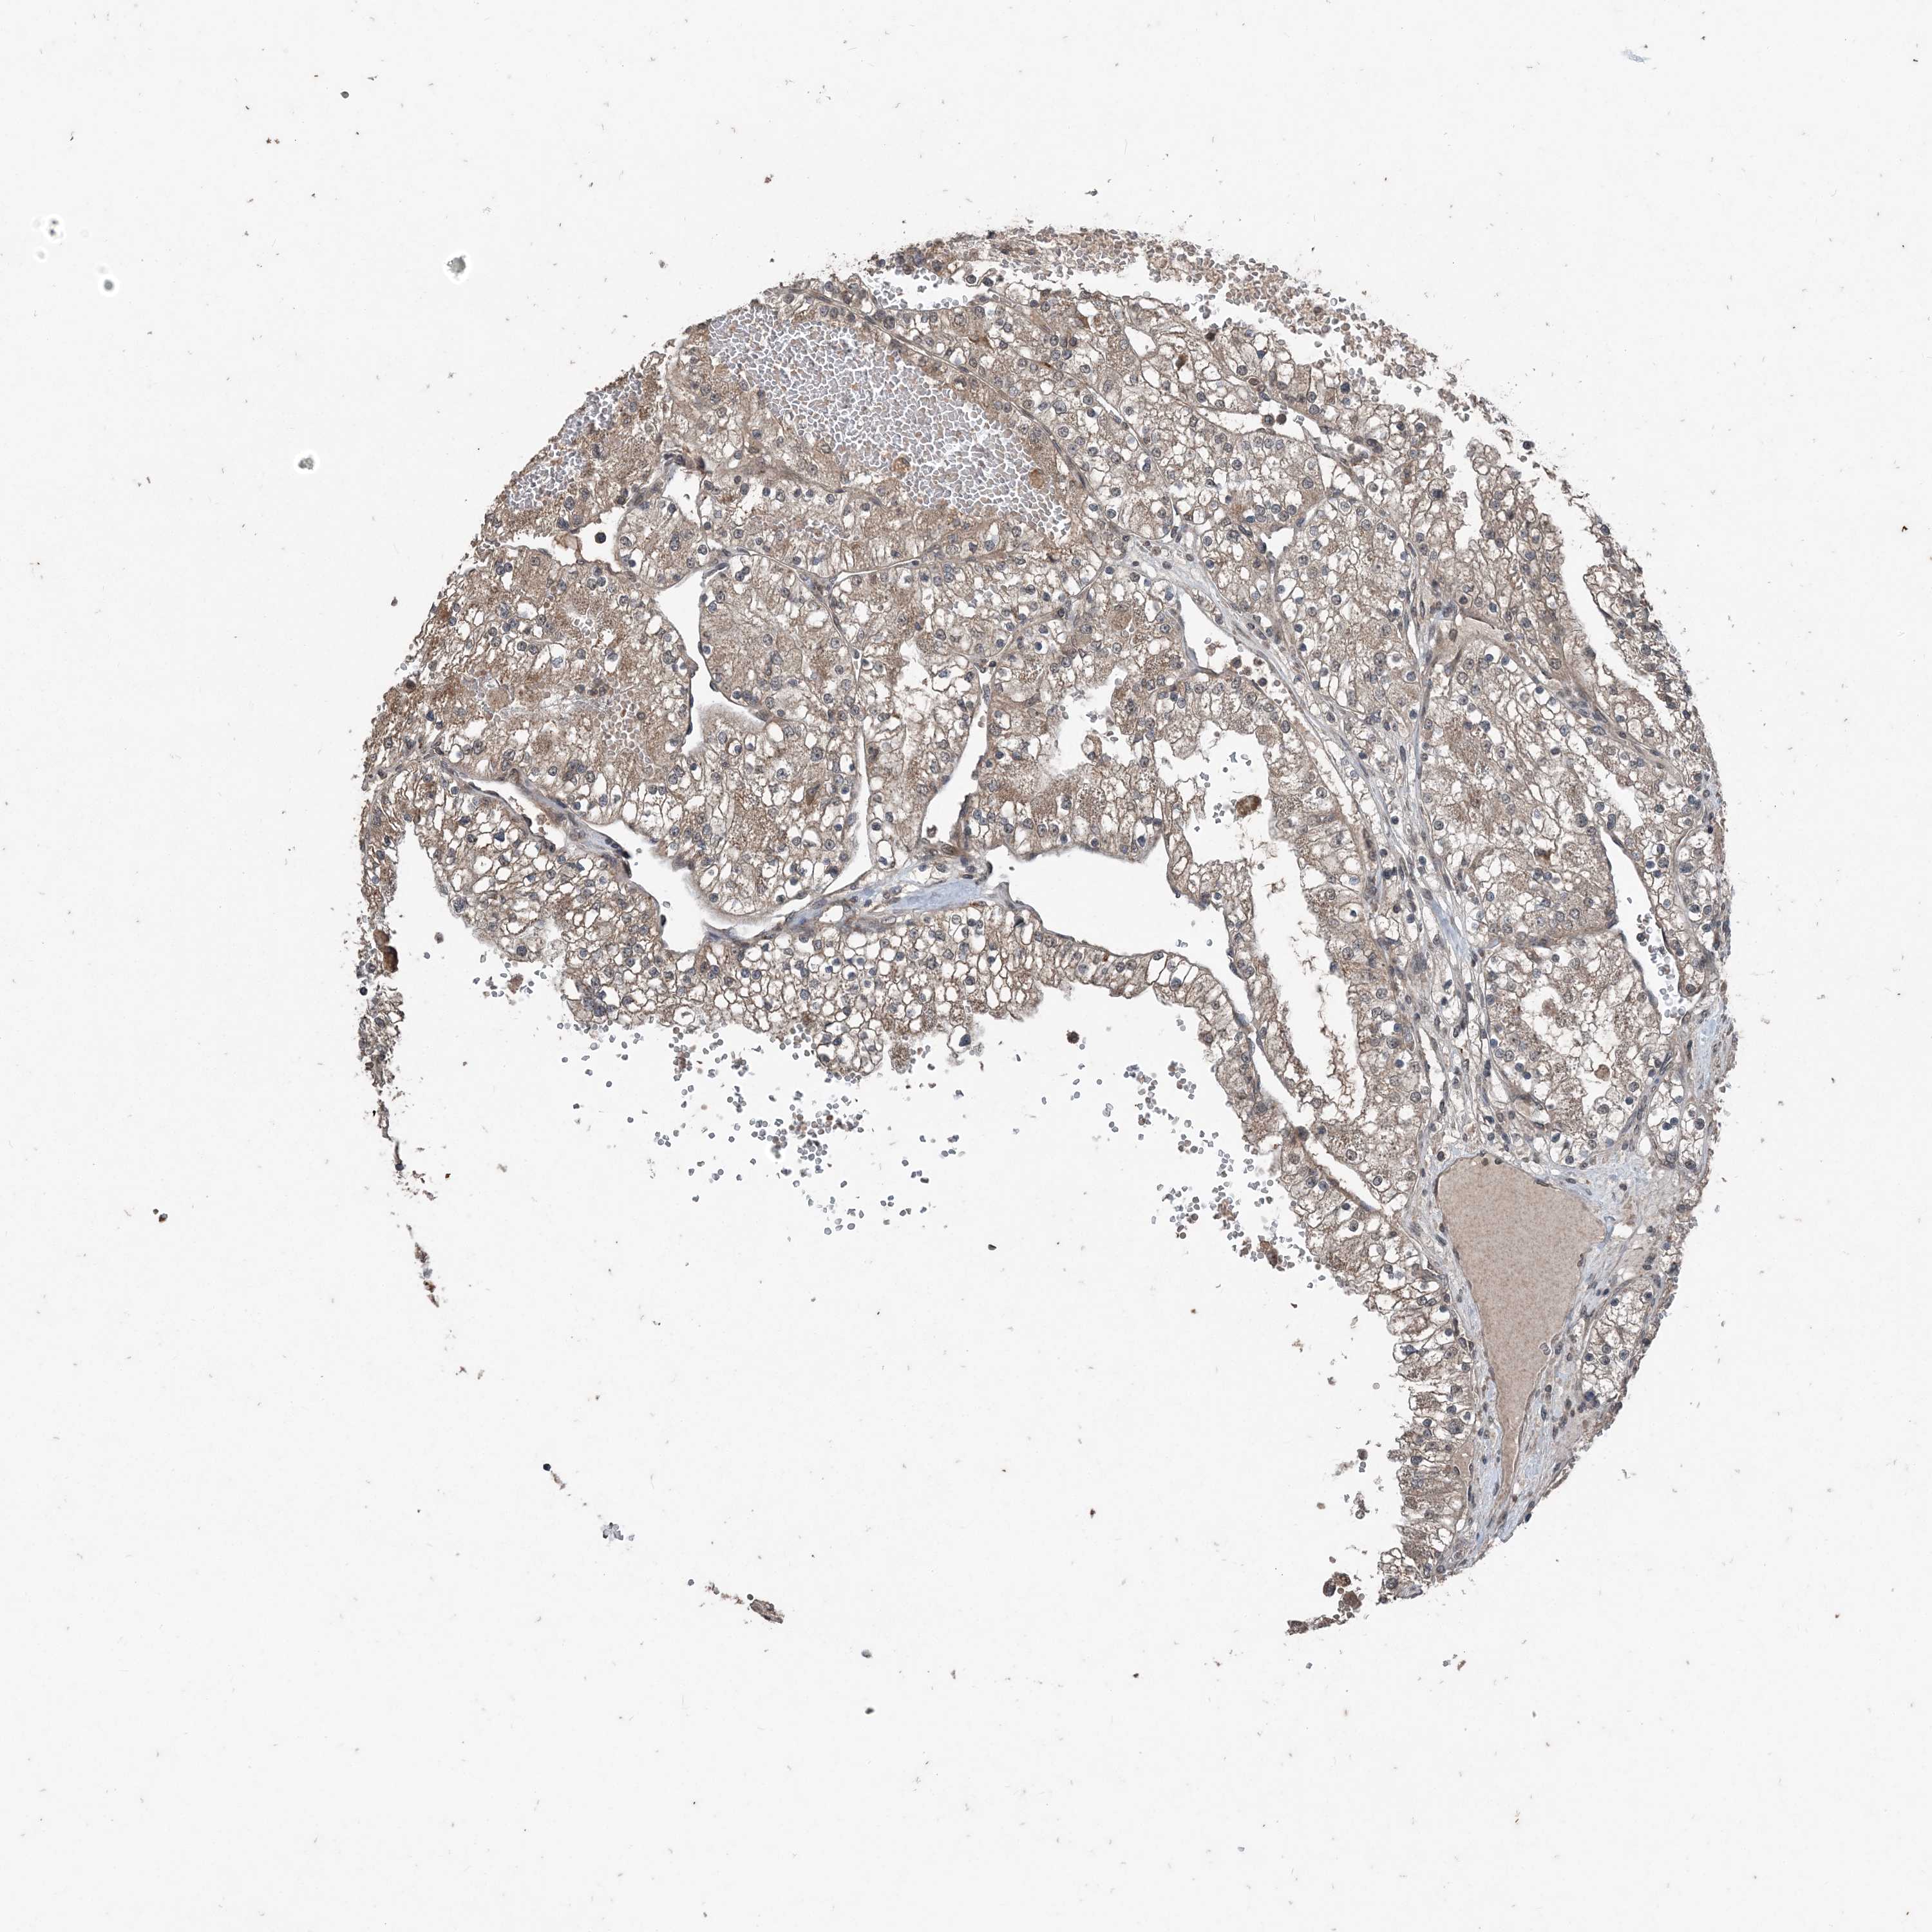

KIDNEY RENAL CLEAR CELL CARCINOMA (TCGA) - Interactive survival scatter ploti

The Survival Scatter plot shows the clinical status (i.e. dead or alive) for all individuals in the patient cohort, based on the same data that underlies the corresponding Kaplan-Meier plots. Patients that are alive at last time for follow-up are shown in blue and patients who have died during the study are shown in red.

The x-axis shows the expression levels (FPKM) of the investigated gene in the tumor tissue at the time of diagnosis. The y-axis shows the follow-up time after diagnosis (years). Both axes are complimented with kernel density curves demonstrating the data density over the axes. The top density plot shows the expression levels (FPKM) distribution among dead (red) and alive patients (blue). The right density plot shows the data density of the survived years of dead patients with high and low expression levels respectively, stratified using the cutoff indicated by the vertical dashed line through the Survival Scatter plot. This cutoff is automatically defined based on the FPKM cutoff that minimizes the p-score. The cutoff can be changed by dragging the vertical line or by entering a cutoff value in the square labeled "Current cut-off".

Under the Survival Scatter plot the p-score landscape (black curve; left axis) is shown together with dead median separation (red curve; right axis). Dead median separation is the difference in median mRNA expression between patients who have died with high and low expression, respectively. It is calculated as follows: median FPKM expression of dead patients with high expression - median FPKM expression of dead patients with low expression. This is intended to aid the user in visually exploring custom cutoffs and the associated p-scores and dead median separation.

Individual patient data is displayed and can be filtered by clicking on one or more of the category buttons on the top of the page. Categories describing expression level and patient information include: high, low, alive, dead, female, male and tumor stages. The scale of the x-axis can be toggled between linear and log-scale by clicking on the "x log" button. Mouse-over function shows TCGA ID, patient information and mRNA expression (FPKM) for each patient.

& Survival analysisi

Kaplan-Meier plots summarize results from analysis of correlation between mRNA expression level and patient survival. Patients were divided based on level of expression into one of the two groups "low" (under cut off) or "high" (over cut off). X-axis shows time for survival (years) and y-axis shows the probability of survival, where 1.0 corresponds to 100 percent.

CFL1 is potential prognostic, high expression is favorable in Kidney Renal Clear Cell Carcinoma (TCGA)

Best expression cut offi

Based on the FPKM value of each gene, patients were classified into two groups and association between prognosis (survival) and gene expression (FPKM) was examined. The best expression cut-off refers the FPKM value that yields maximal difference with regard to survival between the two groups at the lowest log-rank P-value. Best expression cut-off was selected based on survival analysis .

When clicking on this number, the vertical dashed line indicating cut-off, the interactive survival plot, and the Kaplan-Meier curve will be adjusted to show results based on the best expression cut-off.

: 618.95

TCGA RNA samplesi

RNA-seq data is reported as average FPKM (number Fragments Per Kilobase of exon per Million reads), generated by the The Cancer Genome Atlas (TCGA) .

Normal distribution across the dataset is visualized with box plots, shown as median and 25th and 75th percentiles. Points are displayed as outliers if they are above or below 1.5 times the interquartile range. FPKM values of the individual samples are presented next to the box plot.

Average pTPM 779.4

Number of samples 521